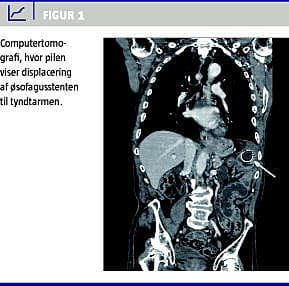

En 80-årig mand blev diagnosticeret med inoperabelt adenokarcinom i den distale del af øsofagus. Canceren var stenoserende, og patienten havde udtalte synkeproblemer, hvorfor der med god effekt blev anlagt en coated, selvudfoldende øsofagusstent. Efterfølgende gennemgik patienten behandlingen med en kombination af kemo- og radioterapi med radiologisk god respons på øsofaguscanceren. Tre måneder senere opstod ileuslignende symptomer i form af kolikagtige smerter ved fødeindtagelse, kvalme og opkastninger. Der blev foretaget computertomografi (CT) af thorax og abdomen, som viste, at stenten var displaceret til tyndtarmen ca. 50 cm fra Treitz' ligament og med ødem og inflammation omkring stenten (Figur 1 ). Tyndtarmen var lettere dilateret oralt for stenten, men på CT`en var der ingen tegn til perforation eller fri intraperitoneal væske. Efterfølgende tyndtarmspassage bekræftede CT-fundet. Der blev foretaget laparotomi, og her fandt man, at stenten delvist var migreret ud af tyndtarmslumen ca. 50 cm fra Treitz' ligament med truende perforation. Der var lokal abcesdannelse, men der fandtes ingen generaliseret peritonitis. Der blev foretaget resektion af 20 cm tyndtarm, inklusive stenten, og der blev udført en primær tyndtarmsanastomose. Patienten blev udskrevet i velbefindende ni dage efter operationen.